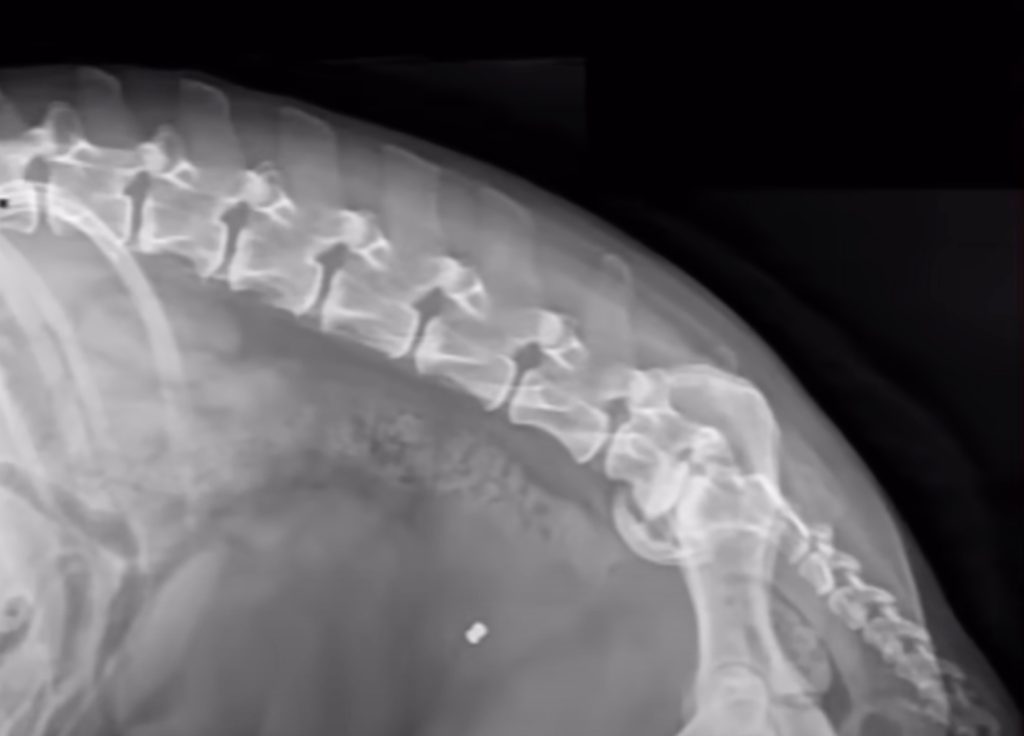

After Jem was warm enough to undergo tests, the team performed X-rays to understand the extent of his injuries. What they discovered was nothing short of horrifying. Jem had been shot multiple times — up to four bullets were still lodged inside his small frame. One bullet lay dangerously close to his spine. Combined with a degenerative condition called spondylosis, this injury had left him completely paralyzed in his hind legs. The doctors explained that he could no longer stand or walk on his own. Every movement came with visible pain, and his body had grown so weak that they feared he might not survive through the night.